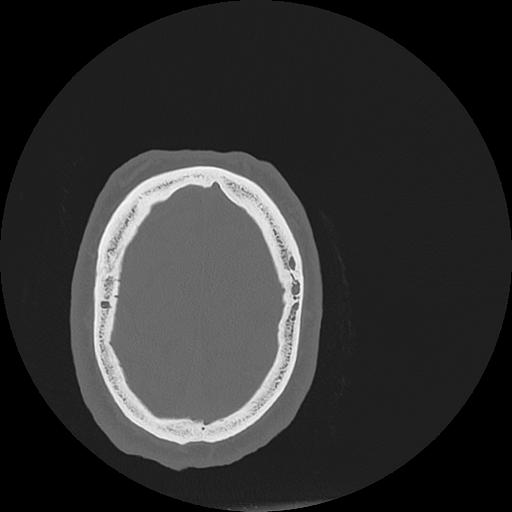

7 HUESO,,Vol,0.5,HUESO,,